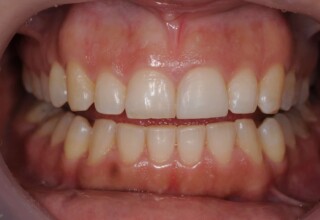

Αποκατάσταση διαστημάτων μεταξύ κεντρικών και πλαγίων τομέων

Τα διαστήματα έχουν δημιουργηθεί κυρίως λόγω των στενών πλαγίων. Μετά την ολοκλήρωση της ορθοδοντικής θεραπείας τα διαστήματα “έκλεισαν” με την τοποθέτηση δύο αποκαταστάσεων σύνθετης ρητίνης.